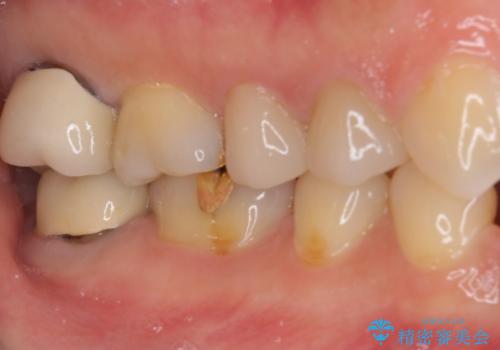

- 奥歯の間にものが挟まって不快であるとのことで来院された患者様です。

検査を行った結果、非常に強い咬合力により隣の歯との隣接面にひびが入り、虫歯が拡大している状態でした。

部分的にゴールドインレーが装着されていたので、虫歯と合わせて除去し、新たにゴールドインレーにて修復治療を行うこととしました。